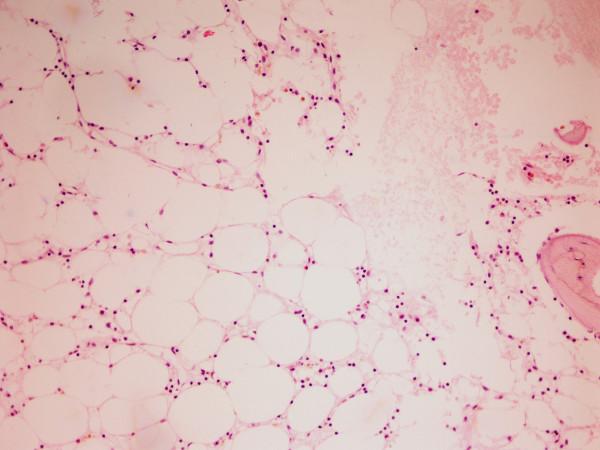

We report the case of a 46-year-old Greek man who developed severe aplastic anemia during treatment with pegylated interferon alpha 2a for chronic hepatitis C virus infection. He presented with generalized purpura and bruising, as well as pallor of the skin and mucous membranes. His blood tests showed pancytopenia. He underwent allogeneic bone marrow transplantation after completing two courses of immunosuppressive therapy with antithymocyte globulin and cyclosporin A.